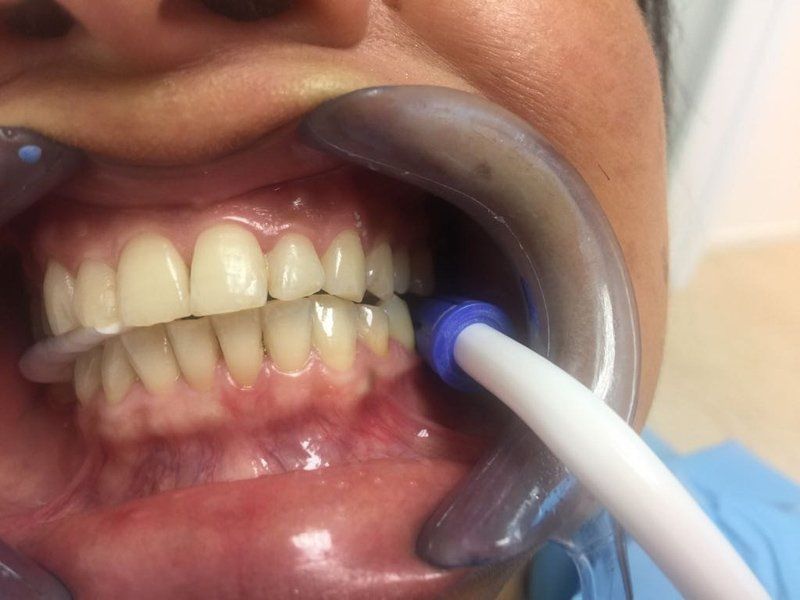

Sbiancamento con led

Prima e dopo una sola seduta d’igiene orale professionale in paziente maschile fumatore, il risultato può essere ulteriormente migliorato con un trattamento di sbiancamento.